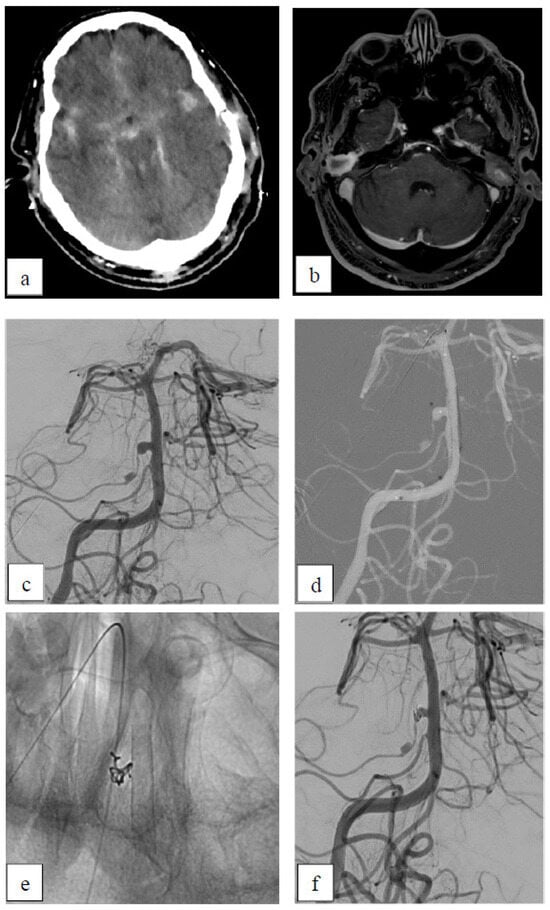

Case 4: Dissecting Aneurysm

| 4 | 48 | m | V4 | left | dissecting | yes | no | ASA+ Clopidogrel | A3 | 6 | D1 |